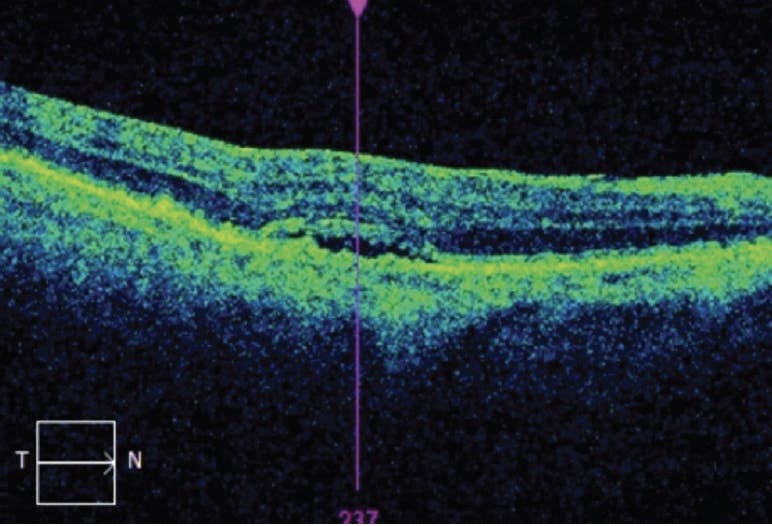

She returned to our practice for a clinical examination before her second anti-VEGF injection. Her BCVA had returned to 20/20 OD, and the subretinal fluid had resolved (Figure 3).

This case illustrates how supplementing in-person clinical examination and imaging with at-home monitoring can lead to early detection of conversion from intermediate to wet AMD. Thanks to early detection, the patient was able to receive timely therapy and experienced rapid resolution of retinal fluid. Continued therapy will be required to maintain her vision.